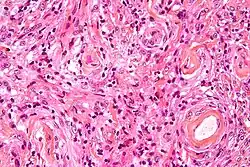

- A woven architectural pattern

- Psammoma bodies (spheroid calcifications)

- Syncytial cells (having indistinct cell membranes) with eosinophilic (pink) cytoplasms

- Round uniform nuclei

- Whorls (concentric cell arrangements)[16]

Histologically, meningioma cells are relatively uniform, with a tendency to encircle one another, forming whorls and psammoma bodies (laminated calcific concretions).[19] As such, they also have a tendency to calcify and are highly vascularized.

- ^ Image by Mikael Häggström, MD. Reference for typical findings: Chunyu Cai, M.D., Ph.D. "Meningioma". Pathology Outlines.